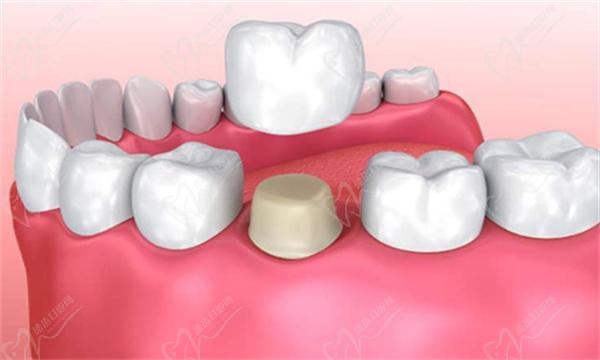

2】牙齿修复:对于较重的牛牙症,可以考虑使用牙齿修复方法,如烤瓷冠或全瓷冠来改变牙齿的形状和大小。这些方法通常需要将牙齿磨小并覆盖上人造冠,以改善牙齿的外观和功能。

牙齿修复